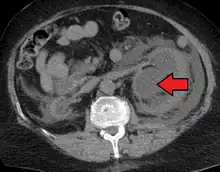

- CT scan of bilateral hydronephrosis due to a bladder cancer

- Massive hydronephrosis as marked by the arrow.